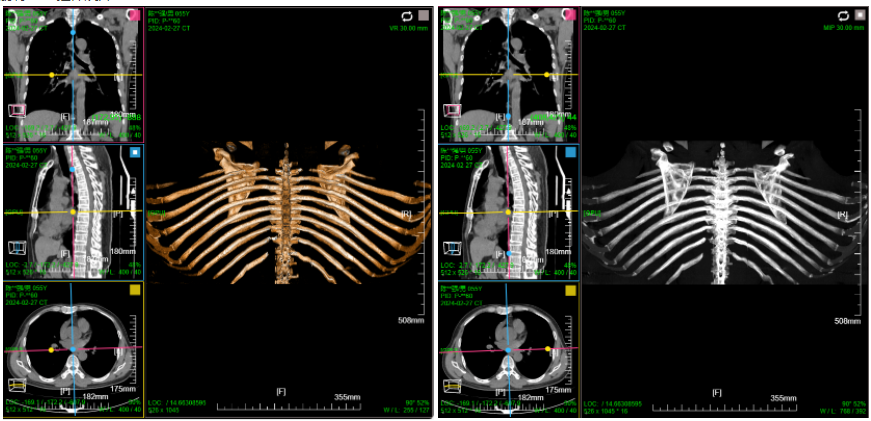

三维:MPR多平面重建(支持任意旋转)、CPR任意曲线切面重建、MIP最大密度、VR容积重建、VE虚拟内窥;任意三维裁剪、一键去床、一键去头骨、快速旋转、厚切MPR(最大密度/最小密度/均值/VR); 手工/半自动分割,分割目标三维渲染; 肋骨CPR拉伸渲染、牙神经管渲染、血管CPR拉直渲染等

八、三维浏览功能操作和截图

左键双击MPR窗口可在MPR三窗口和1x1窗口间切换;三维渲染窗口左键双击在在1x1视图模式和当前视图模式切换

CPR曲面重建 、厚切曲面;

VR容积渲染;鼠标右键默认实时调整当前VR传输函数

MIP 最大密度投影渲染: 鼠标右键默认实时调窗